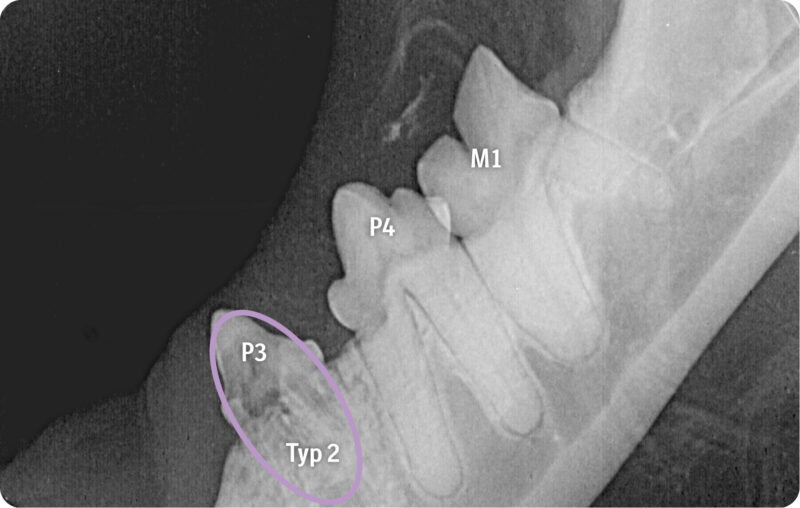

Über entsprechende Röntgenbefunde kann die Zahnresorption aufgezeigt werden. Durch die Visualisierung des Kalenders haben Tierärzt:innen ein gutes Medium, um zu erreichen, dass ihre Botschaft von Tierhalter:innen nicht nur gehört, sondern auch verstanden wird. Wichtig dabei ist die Unterscheidung der einzelnen Typen der Erkrankung. Die intraorale Aufnahme des Unterkiefers rechts zeigt eine Zahnresorption Typ 1 bei M1 mit fokaler Zahnresorption im Kronenbereich sowie den Übergang zur Wurzel bei erhaltenem Parodontalspalt. Bei P3 und P4 werden durch die Aufnahme fehlende Kronenbereiche mit nur noch schwach nachvollziehbaren resorbierten und in Knochengewebe umgebauten Wurzeln erkennbar sowie der Verlust des Parodontolspalts, also eine Zahnresorption vom Typ 2.

Die Bildgebung zeigt, wie unterschiedlich Zahnresorptionen bei der Katze im Röntgen aussehen können. Wichtig für die Praxis zu wissen ist, dass sie je nach Typ unterschiedlich behandelt werden müssen: So ist eine Kronenamputation nur bei einer Typ-2-Zahnresorption mit vollständigem Verlust des Parodontalspalts möglich. Bei Zahnresorption Typ 1, also bei einem erhaltenen Parodontalspalt, müssen alle Wurzeln extrahiert werden.